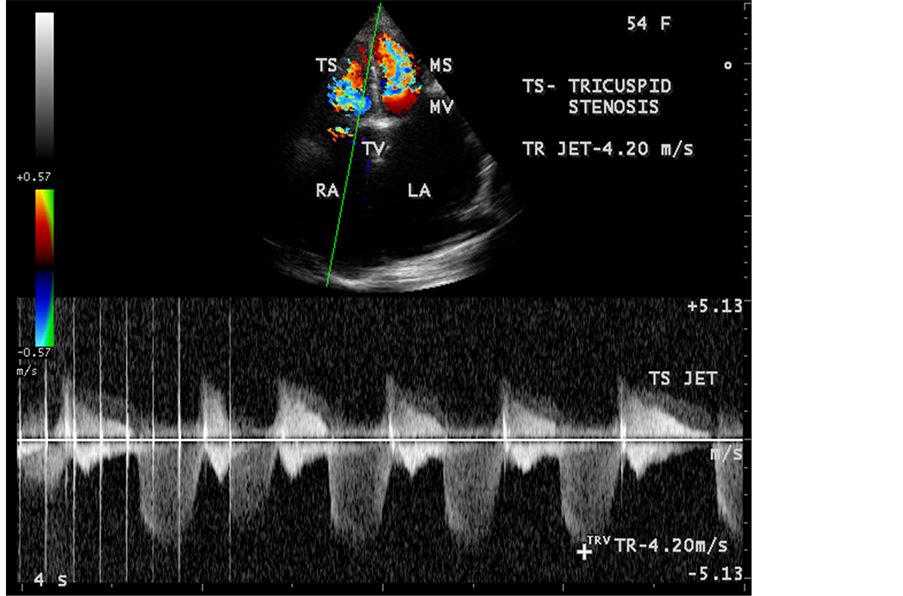

Figure 58. Showing the rheumatic tricuspid stenosis and tricuspid regurgitation jets in a 54-year- old female.